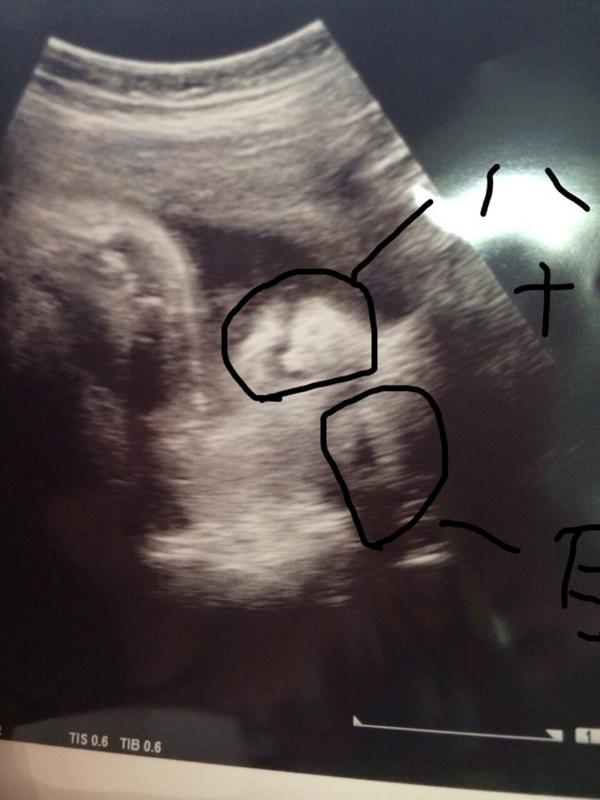

おなかの赤ちゃんに出会えるエコー写真 エコー写真が確認できる定期検診は、妊婦さんの楽しみの一つです。自分のおなかの赤ちゃんの成長が確認できますから。専門的な知識がないとエコー写真を見てもわかりませんが、エコー写真の簡単な見方をご紹介します。 エコー写真でわかること 赤ちゃん3dエコー写真はいつからいつまで? 3dエコー写真のおすすめ時期は 早くても妊娠14週から、遅くても32週ごろ と言われています。 赤ちゃんの成長によって見え方が変わってきます。 全身を見たいか、顔の表情だけで十分なのか、病院と相談しつつ時期を決めるのがいいですね。エコー写真でダウン症の子だと判別できるのか 首のむくみがあったりすると可能性が高いらしく、引っ張りだして比較。 参考になるかわからないけれど 我が子のエコー写真多めにアップしていきます 何度も言います! 不安になって落ち込んでも私責任とれませんので、引き返して下さい

鼻の付け根の部分が低く、横に広がるような形をしている事が多いです。 特に横から見ると判断が付きやすいです。 新生児のうちは通常の赤ちゃんでも鼻は低いのが普通ですが、 ダウン症の赤ちゃんは横に広がりがあるのが特徴です。ダウン症のエコー写真の鼻の特徴 エコー検査ではおなかの中にいる赤ちゃんを 超音波を使用したエコーで調べることができます。 今はエコー検査も進歩しているので 昔より立体的に見ることもできるようになっています。 エコー検査では、ある程度妊娠週 33w0d どうしてもお顔が見たくて他院にてはじめての3Dエコーを撮りました。 30週くらいまでのほうがよくみえるそうですが、33週にしてはきれいに撮れたそうです。 赤ちゃんぽくてかわいいお顔が見れたので、他院まで来た甲斐がありました♡ お

4dエコーほど、鼻がシュッとしていません。 妊娠27週にこの4dエコーの写真を見た時は、「鼻の形が綺麗な子が生まれてくる!」と期待したものでしたが、残念ながら実際は異なりました。笑 スポンサーリンク 比較妊娠36週&生後3日 そして最後に、妊娠36週の3d ダウン症をエコーで見ると特徴は鼻に出るだけではありませんね。 スポンサーリンク ダウン症の特徴は耳にも現れる エコーで確認できるダウン症の特徴は、例えば、耳にも出ます。 通常よりも耳が小さく、 低い位置にある 場合は、これも発育不全の領域に入ります。 従って、ダウン症の 赤ちゃんの鼻と、高いと思いますか? 低いと思いますか? 初めて見るわが子だったので、どちらでもすごく愛おしいのですが 、4Dエコー初めて撮ったので全然特徴がわかりづらく、、 どっちっぽいが教えて頂けたらと思います(^^) 妊娠、出産 赤ちゃんの鼻の下の丸いものは何なので